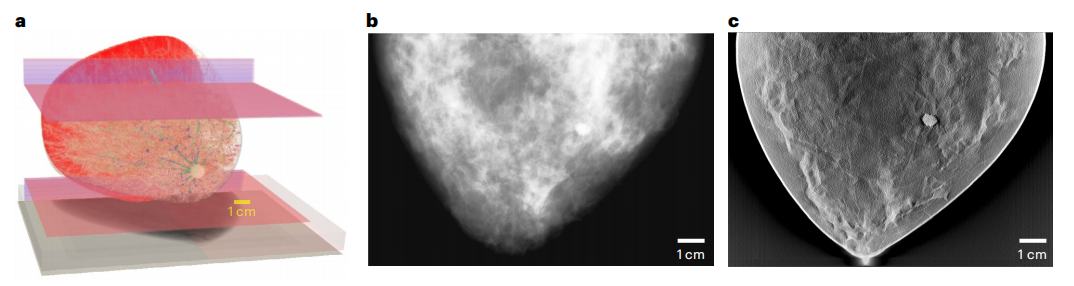

去年,美国食品和药物管理局(FDA)发布了一项行动计划,旨在进一步监督基于AI的医疗器械软件(SaMD)。需要多样化、高质量和经济高效的大数据集来优化从数据采集、图像重建和分析到诊断发现的整个工作流程。在实践中,获取大型临床数据集的成本很高。在这种情况下,上述虚拟扫描将是非常宝贵的。作为数字孪生技术价值概念的证明,FDA的一个团队模拟了监管评估虚拟成像临床试验(VICTRE)研究,其中创建了2986名虚拟患者,以评估数字乳腺体层合成(DBT)作为乳腺癌筛查全数字化乳腺摄影替代品的性能,如下图。研究表明,模拟工具可能是成像设备监管评估的可行证据来源。

FDA 监管评估虚拟成像临床试验研究的代表性结果。图片来源:Nature machine intelligence